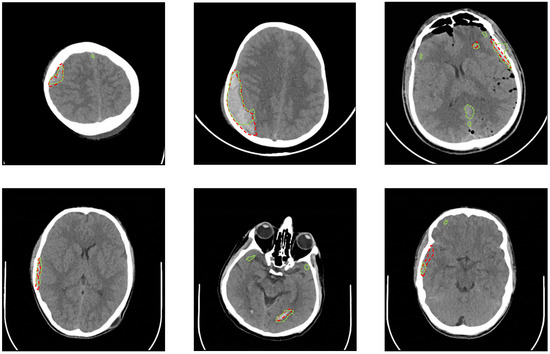

| Intraventricular | 24 | Epidural | 182 |

| Intraparenchymal | 73 | Subdural | 56 |

| Subarachnoid | 18 | No Hemorrhage | 2173 |

| Jaccard Index | Dice Coefficient | Sensitivity (%) | Specificity (%) | |

|---|---|---|---|---|

| Min | 0.00 | 0.00 | 50 | 0 |

| Max | 0.528 | 0.677 | 100 | 100 |

| STD | 0.163 | 0.211 | 9.9 | 29.9 |

| Average | 0.218 | 0.315 | 97.28 | 50.4 |

| Threshold | Sensitivity (%) | Specificity (%) | Accuracy (%) |

|---|---|---|---|

| 0.5 | 97.2 | 50.4 | 56.6 |

| 0.6 | 88.7 | 62.2 | 65.9 |

| 0.7 | 77.6 | 74.5 | 76 |

| 0.8 | 73.7 | 82.4 | 82.5 |

| 0.9 | 63.1 | 88.6 | 87 |